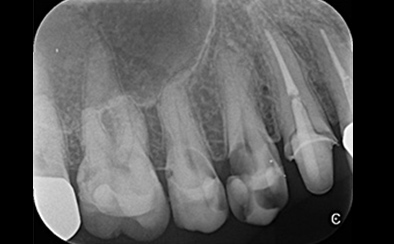

治療前

治療後

黄色い矢印の歯が治療前の対象歯です。レントゲンで観察すると、歯の根のお薬が充分には入っていないようです。

麻酔をして歯の中をマイクロスコープで観察すると、元々あった3つの根だけでなく「もう一つの4番目の根」があったのです。根管治療自体は容易に行えましたが、歯の中を明るく拡大できるマイクロスコープを持っていない歯医者さんでは見つけるのが困難だと思われます。この4つ目の歯の根を治療することにより痛みは消失し「抜歯してインプラント」になるという悪循環に陥らず済みました。根管治療はマイクロスコープを使って精密に、また丁寧に行えば歯を長く保たせることができる治療です。やはり神経自体を残すという選択が、歯の保存にとって一番良いということは間違いありません。